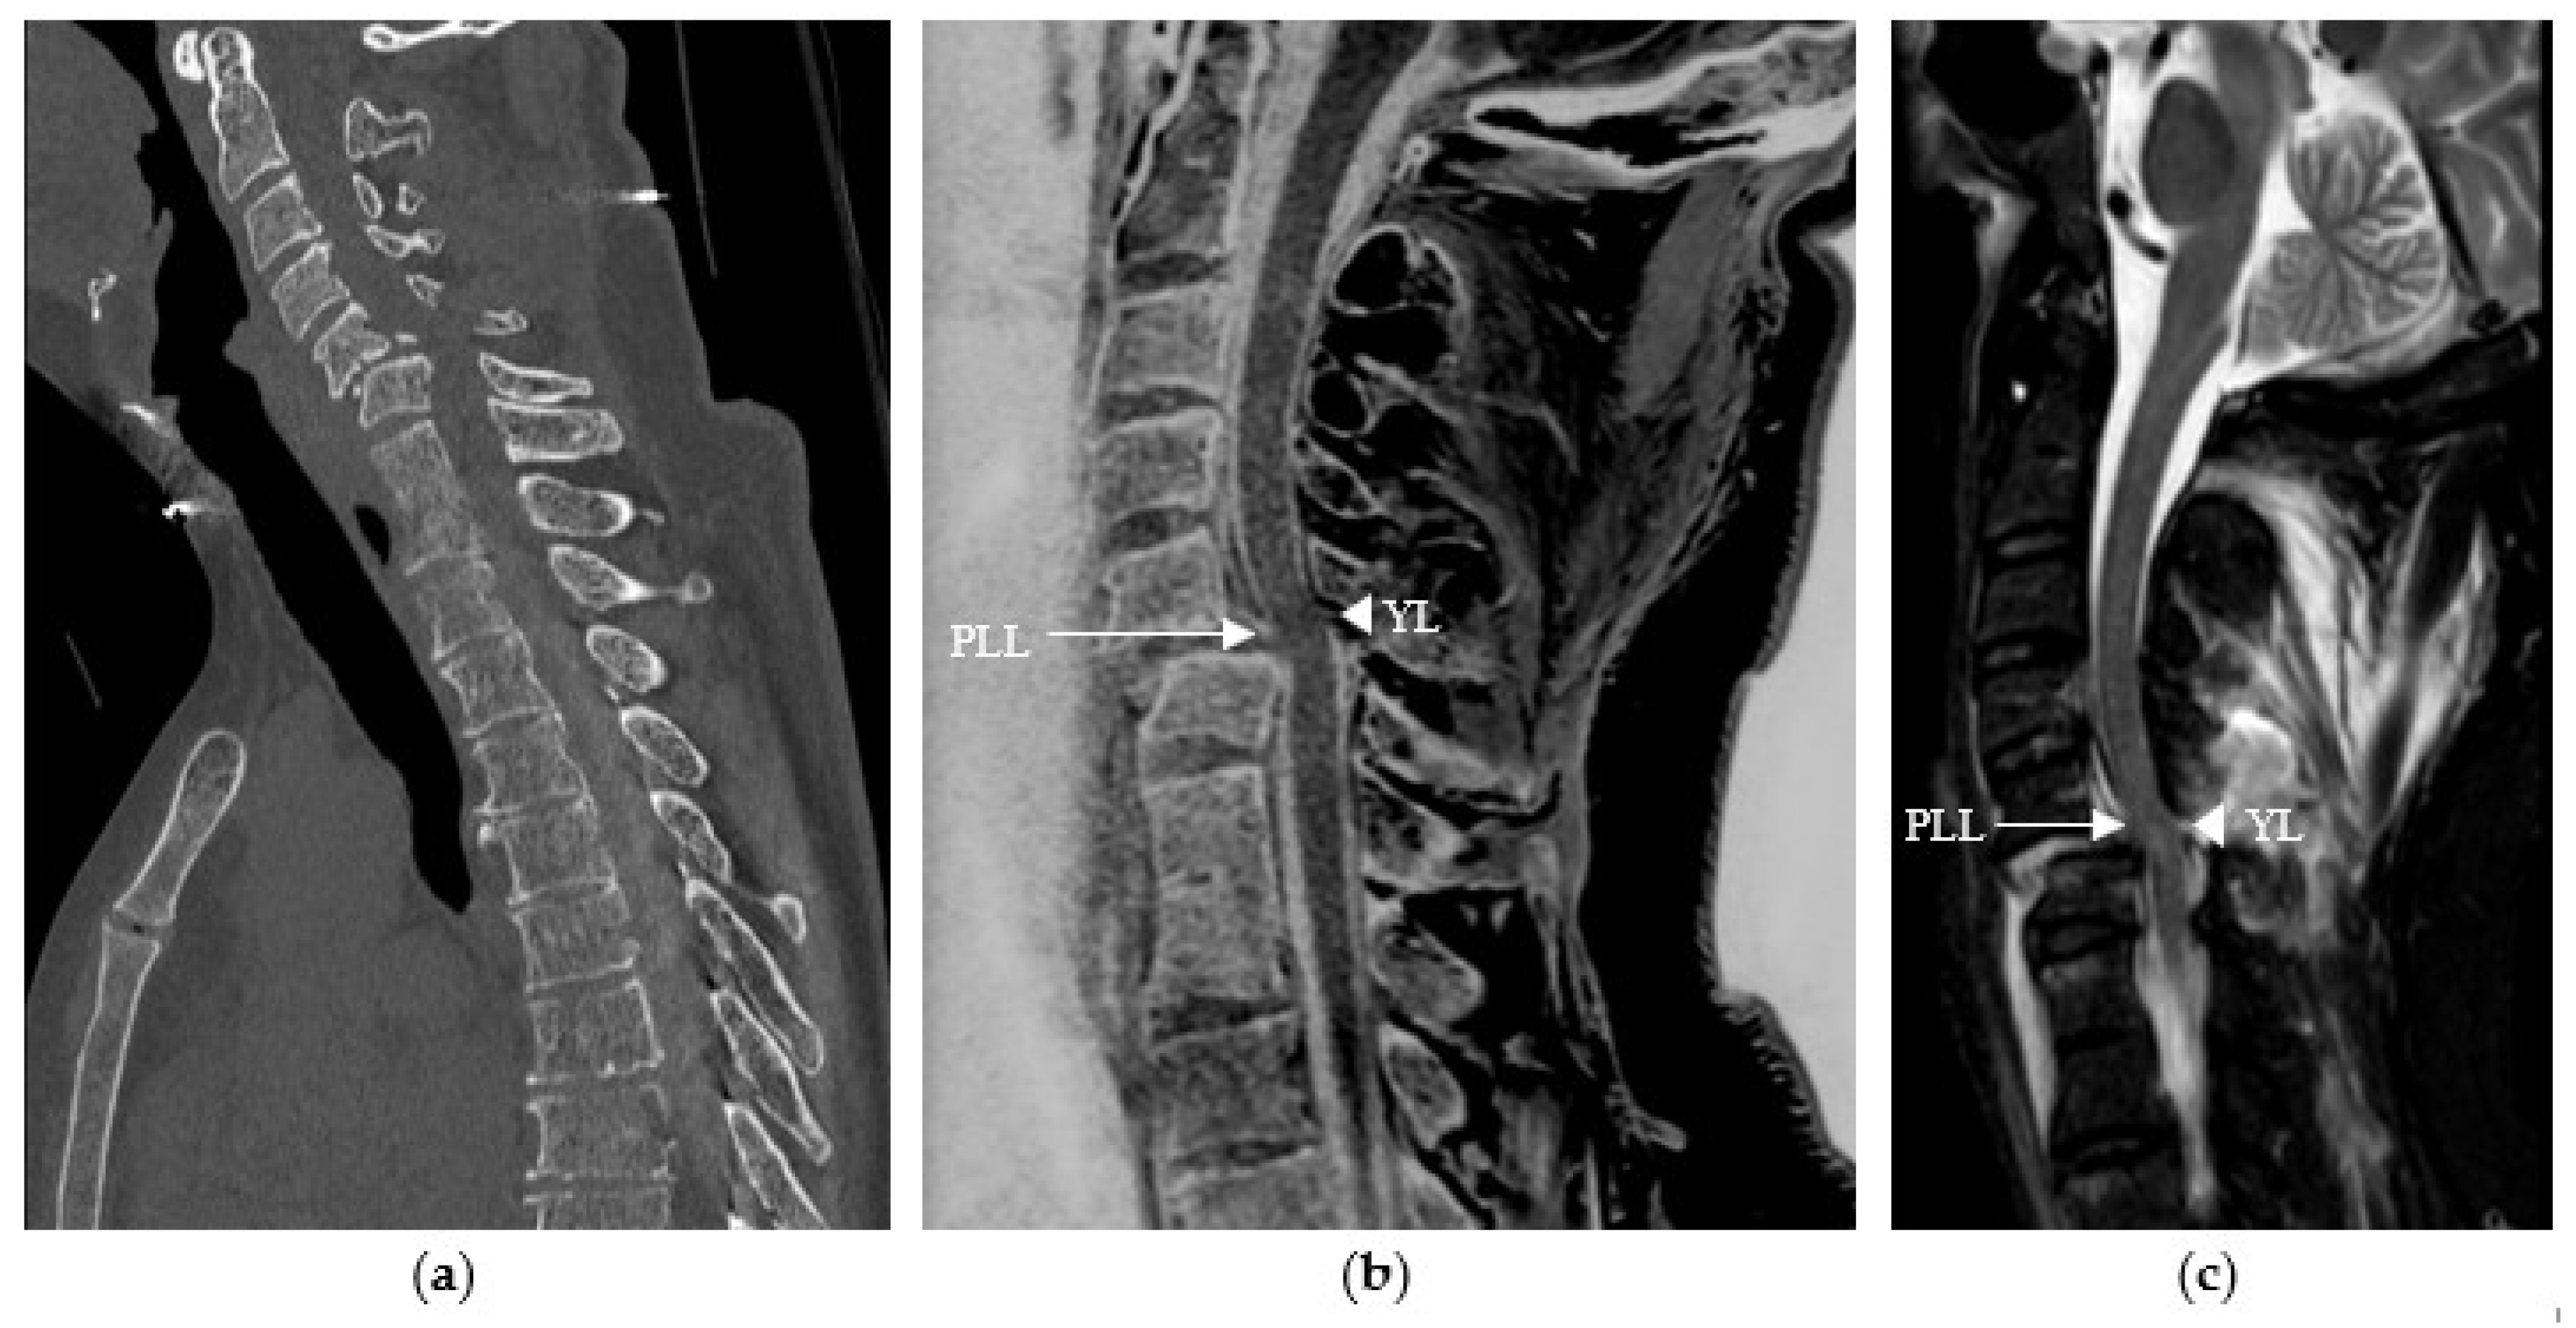

Studies have demonstrated the value of specific CT-like sequences in the assessment of soft tissues, notably the ligament, muscle, and tendon structures [14,15,16], in particular 3D gradient-echo sequences, including the 3D T1 mFFE sequence we used. Our study showed that reading CT-like sequences alone led to the detection of four ligamentous lesions in Observer 1 that were not visualized when reading the CT images alone and three ligamentous lesions in Observer 2, representing 33% of all ligamentous lesions confirmed when reading the CT-like sequences together with the rest of the MRI protocol (n = 12). Our results confirm the data in the literature and are perfectly illustrated in the following images (see Figure 3).

Figure 3.

Traumatic cervical spine injury in a 58-year-old patient at C5–C6, (a) initially evaluated with sagittal CT reconstruction in which ligamentous damage could not be assessed. (b) The sagittal CT-like 3D mFFE sequence revealed damage to the posterior longitudinal ligament (PLL) and the yellow ligament (YL), visualized as a discontinuous white line (arrow and arrowhead), (c) which was confirmed by the remaining MRI sequences, particularly the sagittal T2 STIR sequence.